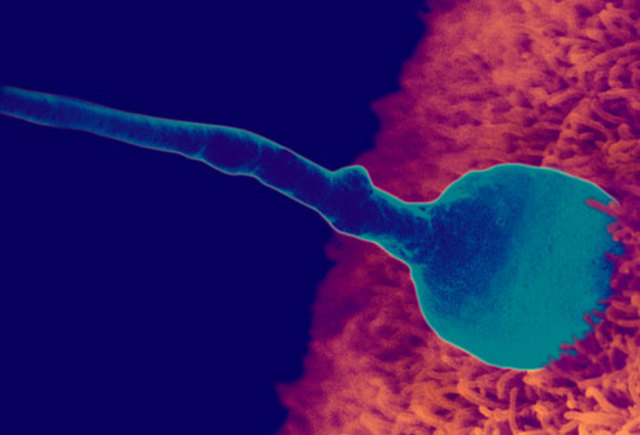

• Fertilization

Fertilization